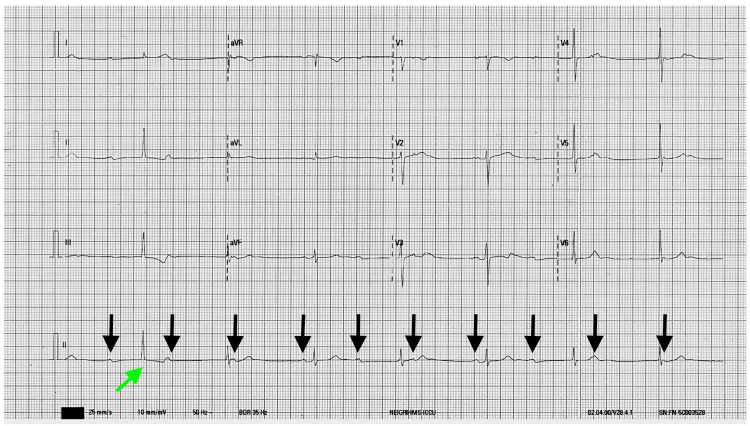

A 26-year-old otherwise healthy male presented to emergency with complaints of dizziness and recurrent syncope. At presentation, his pulse was 42/min, blood pressure: 100/70 mmHg, temperature: 98.1°F, and respiratory rate: 16/min. The rest of the physical examination was unremarkable. ECG on presentation showed a high-grade AV block along with sinus node dysfunction (Figures 1–2).

There was no improvement in the heart rate by repeated administration of atropine (total up to 3 mg). The patient admitted to using cannabis for the last four years, and in the preceding two years, he was smoking 5-8 joints (4-5 g) daily. Prior ECG was within normal limits; therefore, ruling out congenital heart block. There was no family history of any heart disease. The blood counts and metabolic panel were within the normal limit. Serological tests for syphilis, Lyme disease, hepatitis B, hepatitis C, and HIV were negative. Serial troponin-I reports did not show any elevation and the patient’s thyroid-stimulating hormone was normal. Urinary screen 11-Nor-9-carboxy THC was positive (28 ng/ml; cut-off limit: 15 ng/ml). The other biochemistry values are presented in Table 1.

The chest X-ray was normal. There was no clinical/biochemical or radiological evidence to suggest rheumatic, sarcoid heart disease, or myocarditis. On 2D-echocardiography, cardiac chambers and valves were normal with normal left ventricular function (ejection fraction: 66%). The EPS showed a high-grade AV block with atrium to His bundle (AH) interval: 180 ms, His-ventricular (HV) interval: 85 ms, PP interval: 648 ms, RR interval: 1274 ms (Figure 3). Coronary angiography showed normal coronaries.